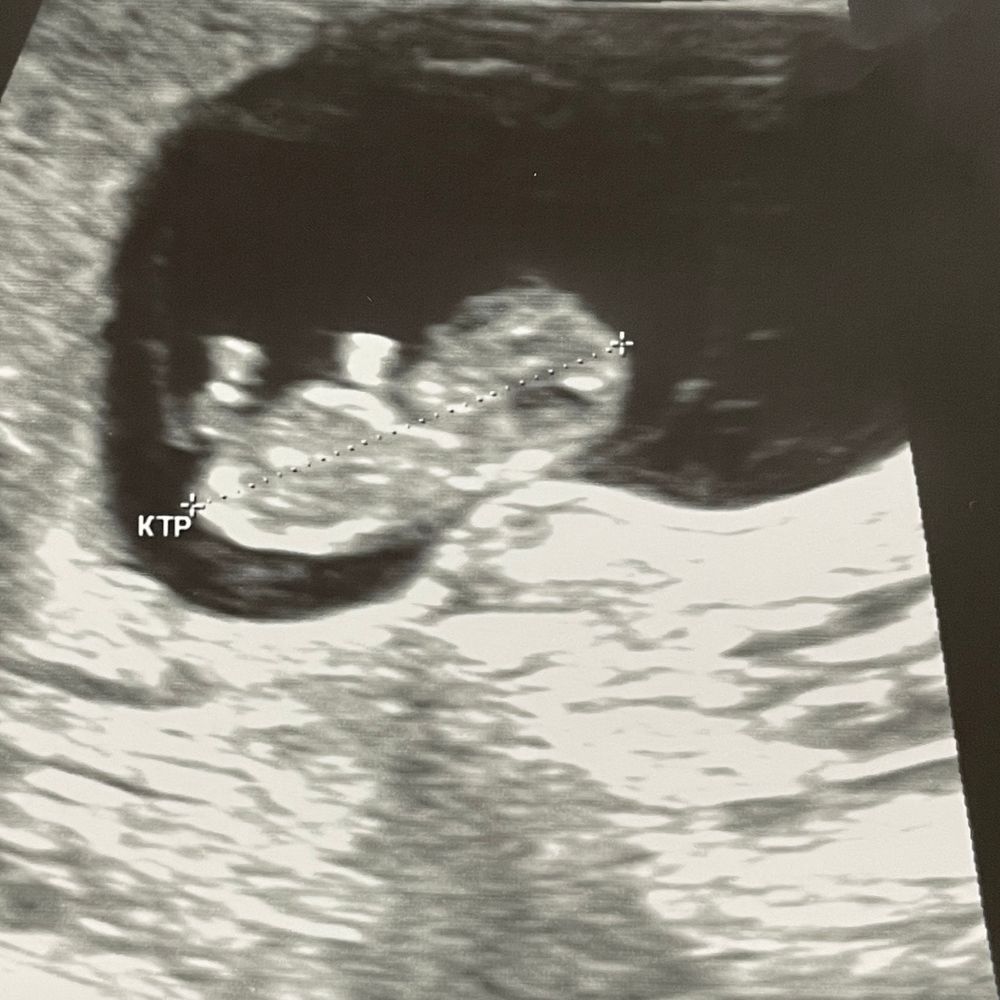

УЗИ 9+4

УЗИ, КТГ, доплерСегодня было очередное узи. Человек подрос, КТР 26 мм, ЧСС 175 уд/мин.

Всё хорошо, соответствует сроку, радуемся дальше 😊